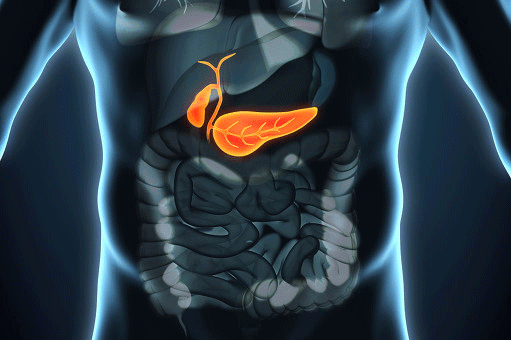

La vésicule biliaire est un organe digestif important de notre corps, dont le rôle principal est de concentrer, de stocker et d'excréter la bile. L'inflammation de la vésicule biliaire affecte notre système digestif. La cholécystite est une maladie clinique courante qui touche les femmes, les personnes âgées, les femmes ayant accouché et les personnes obèses. Si vous souffrez de cholécystite, pouvez-vous la guérir ? Voyons cela ensemble !

Qu'en est-il de la cholécystite chronique ?La vésicule biliaire, présente dans le tube digestif de chacun, en fait l'une des maladies les plus courantes du système digestif.

Quelle est la taille de la vésicule biliaire ? Elle ne mesure que 5 à 8 cm et a la forme du sac d'argent que vous avez l'habitude de voir. Elle est située dans la partie supérieure droite de l'abdomen.Sous le foie se trouve une fosse spéciale pour la vésicule biliaire.。

Quel est le rôle de la vésicule biliaire dans notre organisme ?La vésicule biliaire n'est pas en fait un endroit qui sécrète notre bile comme tout le monde le pense à première vue, ce n'est en fait pas le cas. Le rôle de la vésicule biliaire est en fait de recevoir la bile sécrétée par le foie, de la stocker, de la concentrer et de réguler la pression dans les voies biliaires !Comme nous mangeons généralement quelque chose dans la demi-heure qui suit, la vésicule biliaire déverse sa propre bile concentrée dans nos intestins pour aider ces derniers à digérer et à absorber les graisses et autres aliments.

En outre, la vésicule biliaire joue un rôle d'autoprotection. La vésicule biliaire est divisée en quatre couches : la couche plasmique, la couche musculaire, la lamina propria et la muqueuse.L'une d'entre elles est cette couche de cellules muqueuses qui, outre la puissante fonction d'absorption et de concentration que je viens de mentionner, sécrète également du mucus pour protéger notre vésicule biliaire d'autres facteurs externes.

La vésicule biliaire est située dans la partie supérieure droite de l'abdomen, à la base du foie, et constitue un élément important du système biliaire de l'organisme. Le symptôme typique de la cholécystite est une douleur dans la partie supérieure droite de l'abdomen, dont la nature est le plus souvent colique, et chez certains patients la douleur est si sévère et intolérable que nous l'appelons colique biliaire. La plupart d'entre eux ont pour facteur déclenchant la consommation d'aliments gras, l'examen de la douleur à la pression dans la partie supérieure droite de l'abdomen, le signe de Murphy est positif. L'échographie abdominale permet le plus souvent de voir une hypertrophie évidente de la vésicule biliaire, et la plupart d'entre eux peuvent trouver des calculs de la vésicule biliaire en même temps.

La vésicule biliaire est un organe du corps humain situé à l'extrémité inférieure du foie, une structure en forme de sac qui stocke et concentre la bile, laquelle est ensuite déversée dans le duodénum lors de la consommation d'aliments pour participer au processus de digestion et d'absorption des graisses.